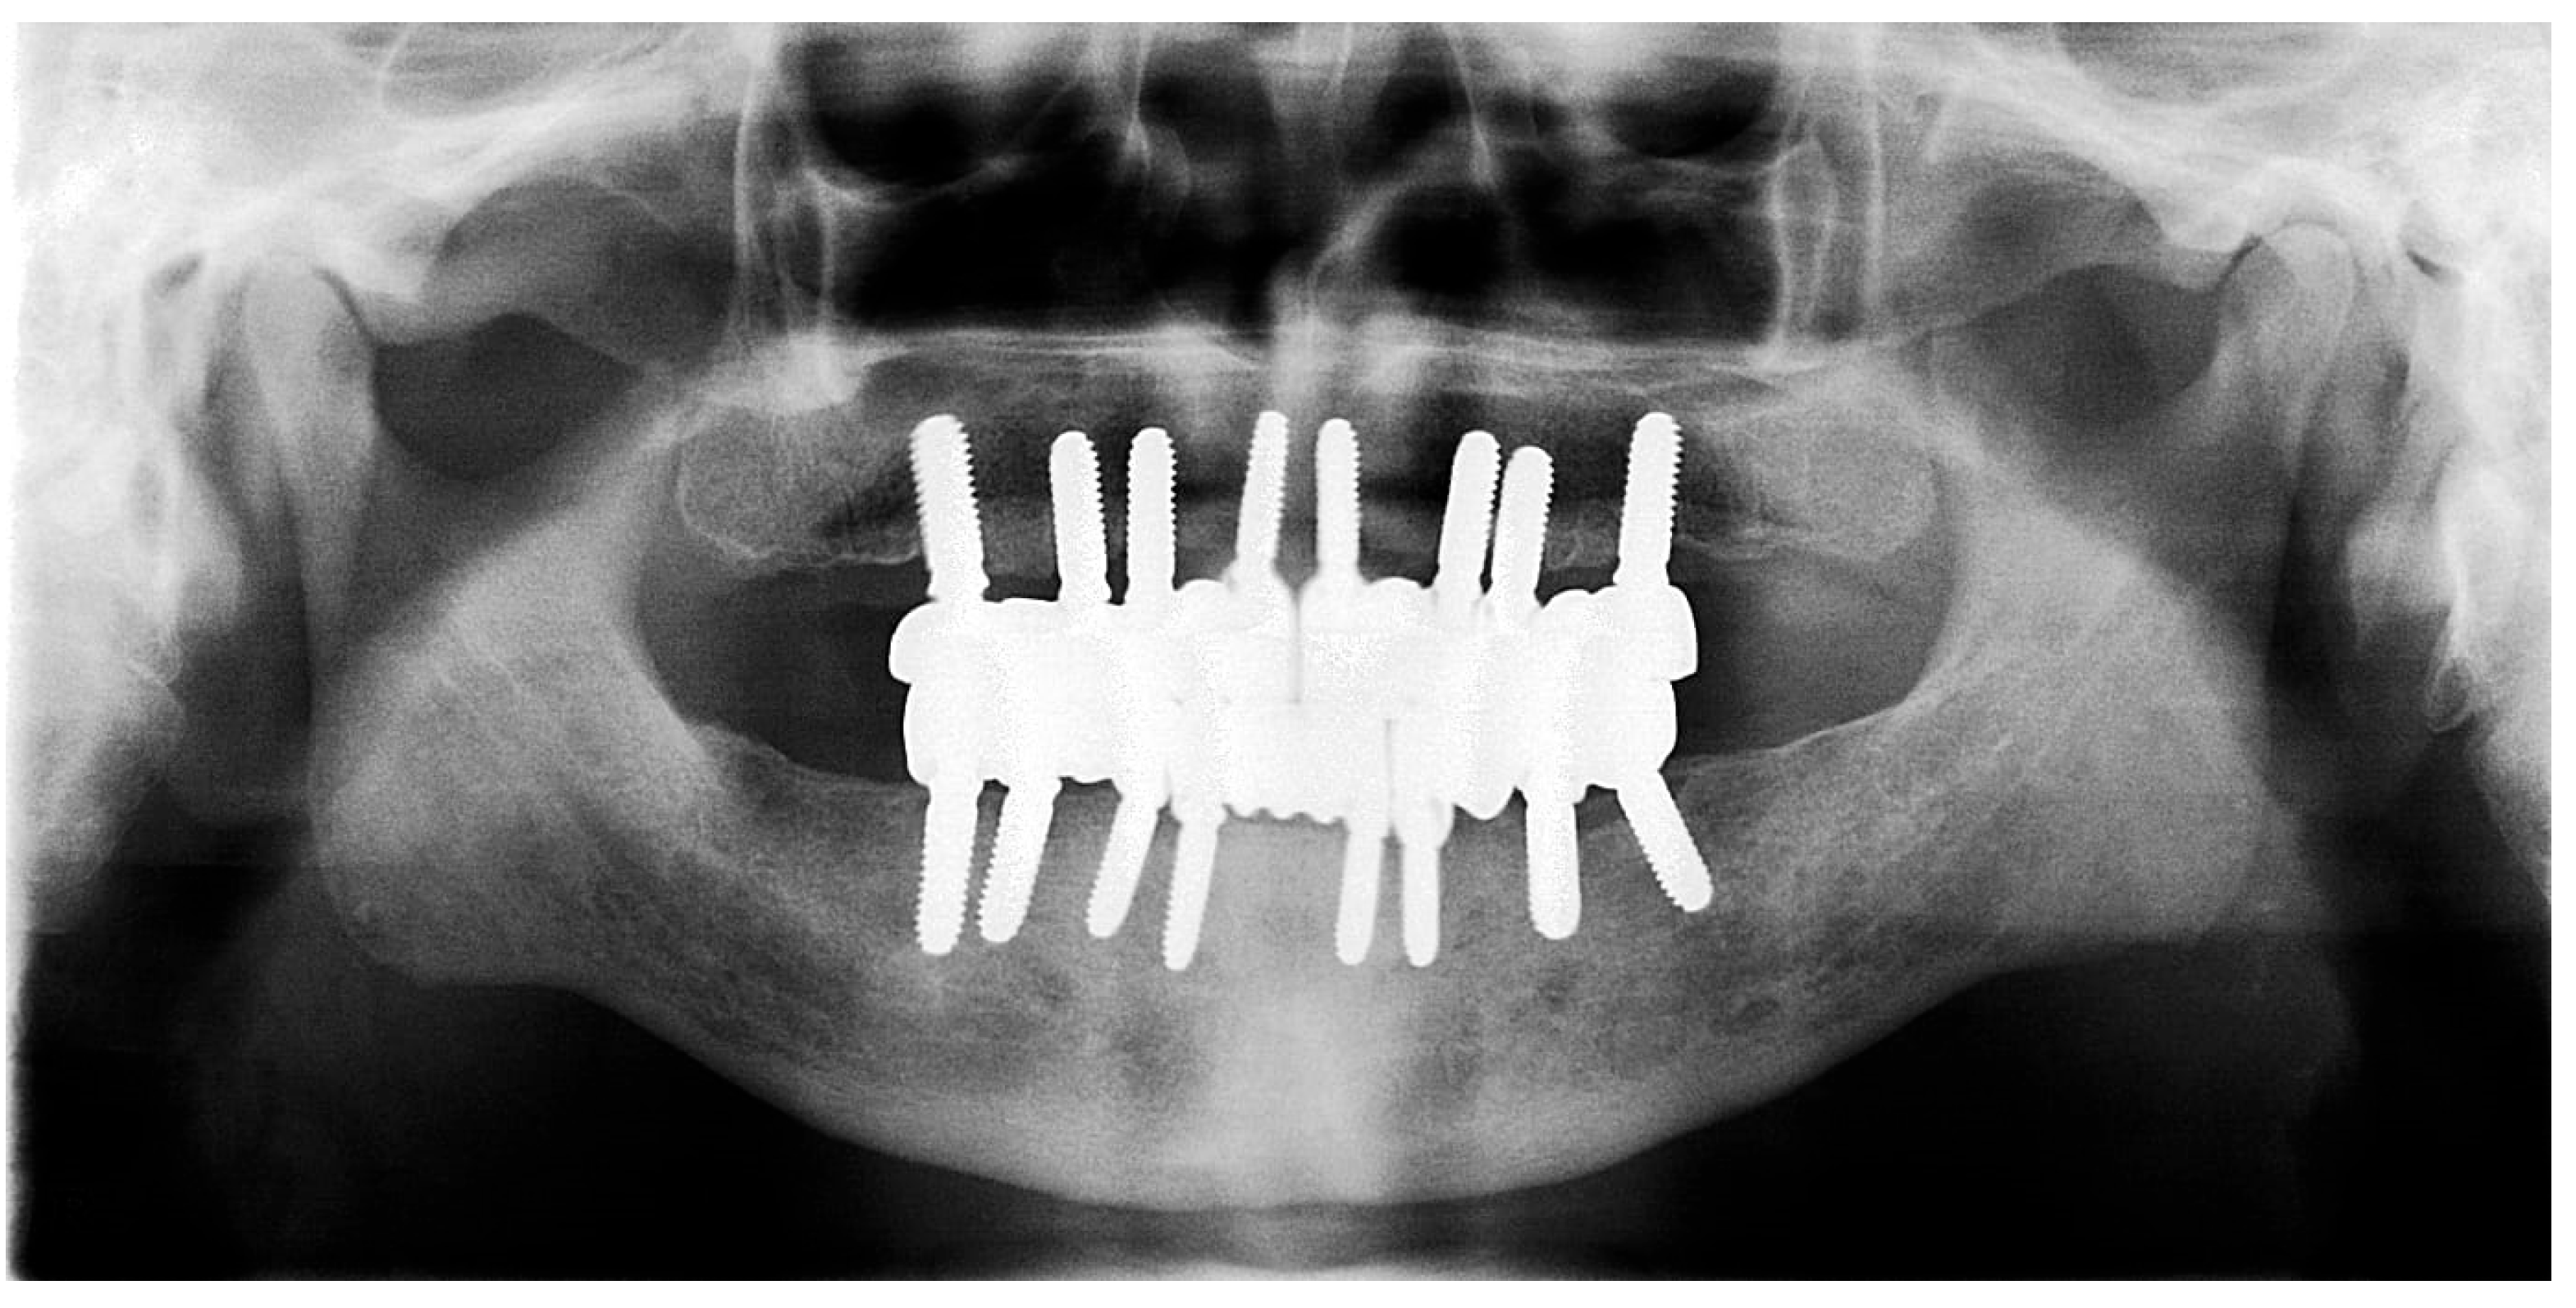

Figure 13. Panoramic X-ray showing the inserted dental implants (taken 10 October 2022).

2.5. Fifth Visit

The restoration plan involved placing a bridge that connects the central incisors to the canines, along with an additional bridge spanning the first premolar to the first molar on each side of the maxillary arch. In the mandibular arch, the plan included three bridges: one connecting the lateral incisors bilaterally and another bridging the canines to the second premolars and first molars on each side (Figure 14 and Figure 15). Placing was confirmed using Panoramic radiographs obtained using the PantOs DG XP panoramic dental X-ray system (Fona S.r.l., Assago, Italy; CE 0051). The unit operates on a 230 V, 50/60 Hz input line with an 8 A fuse. Standard panoramic exposure parameters were applied (90 kVp, 10 mA, exposure time 14 s) following the manufacturer’s safety recommendations. A trained radiology technician performed all scans, and patient positioning was standardized using the built-in cephalostat support and light-beam alignment to ensure reproducibility of serial images.